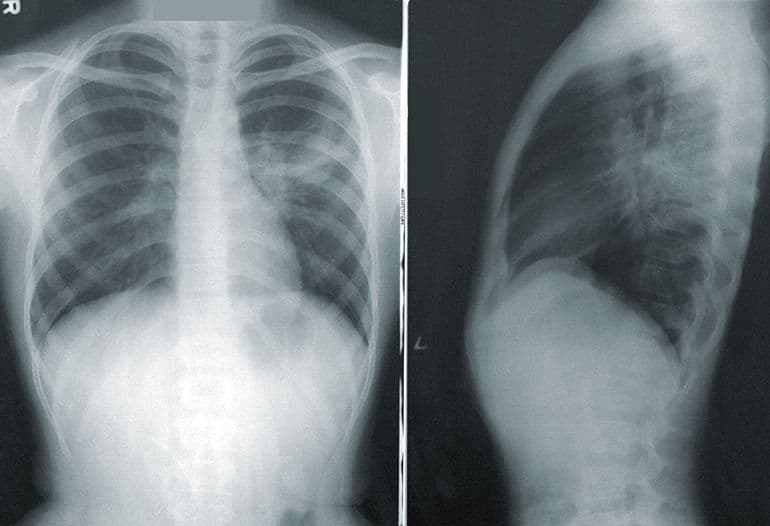

Jeśli podejrzewasz u siebie zapalenie płuc, warto przedyskutować swoje obawy z lekarzem. Pomocna w tym przypadku może okazać się konsultacja online, na którą umówisz się za pomocą czata lub przez aplikację mobilną, bez wychodzenia z domu. Pozwoli ona na dokładniejsze określenie powodu występujących problemów zdrowotnych na podstawie badania. W przypadku, w którym konieczne będzie podjęcie dalszych badań diagnostycznych - lekarz zarekomenduje wizytę w przychodni. Przy zapaleniu płuc może ona okazać się konieczna; RTG płuc to jedna z najpewniejszych metod badania, umożliwiająca jasne potwierdzenie lub wykluczenie zapalenia płuc.